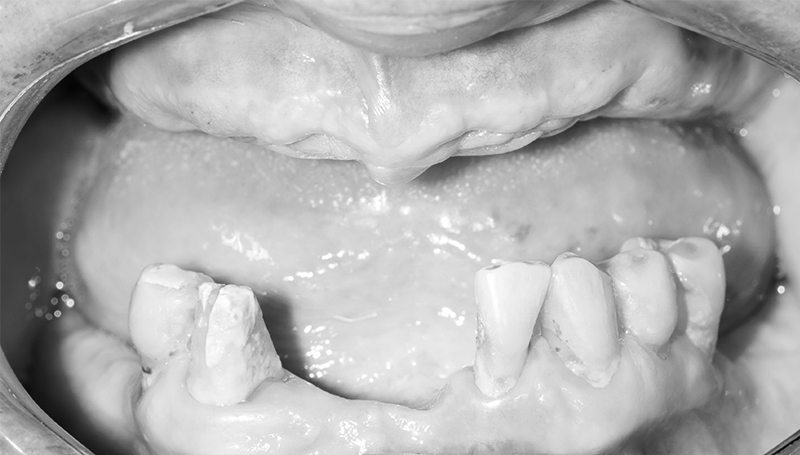

Когда применяется концепция All-on-4?

Мало зубов

Пародонтоз зубов

Отсутствие зубов

После прохождения всех подготовительных процедур пациенту удаляют остатки зубов. Сразу же устанавливаются 4 или 6 имплантов, на которые прикручиваются мультиюниты - на них будет держаться протез. Такая операция проводится под местной анестезией и длится от 2 до 4 часов часов на одной челюсти.

Операция

Наши работы